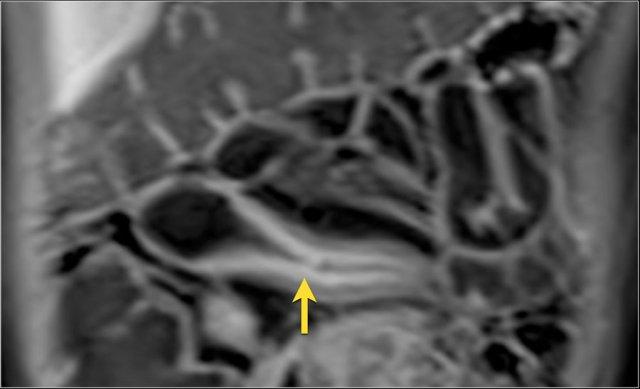

Hình ảnh Balanced FFE mặt phẳng coronal cho thấy rò ruột-bàng quang (mũi tên) xuất phát từ ruột non. Hình ảnh T1W sau tiêm thuốc tương phản cho thấy ngấm thuốc rõ rệt của ruột non và hình ảnh ‘đường ray tàu hỏa’ tại vị trí đường rò.

Rò

Đường xoang và đường rò là các biến chứng thường gặp ở bệnh nhân mắc bệnh Crohn.

Cả hai đều ngấm thuốc rõ rệt trên chuỗi xung T1W sau tiêm gadolinium.

Đường rò có thể biểu hiện dưới dạng cấu trúc phân lớp kiểu ‘đường ray tàu hỏa’ hoặc như một cấu trúc tuyến tính ngấm thuốc.